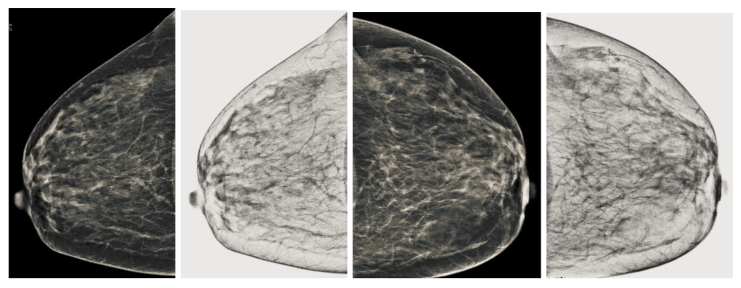

We also measured the PSNR, the image contrast, and the EME of each category of databases, as we analyzed the image in terms of visual observation. The Table 3 shows the performance of our proposed image enhancement method. It can be seen from the Table 3 that our proposed method improved PSNR, contrast, and EME, and this also shows that our method can work on every category of BI-RADS. Because many techniques do not work on higher grade BI-RADS due to the complexity and the images are not of good quality. We obtained an average improvement in PSNR, contrast, and EME in the Table 4. For more observations, we analyzed the visual image of each category and we analyzed the CC and MLO of each category as shown in the Figure 7, Figure 8, Figure 9, Figure 10, Figure 11, Figure 12, Figure 13, Figure 14, Figure 15 and Figure 16. From the figures, every detail of image of every category can be observed, leading to better segmentation of the abnormal region. This image enhancement technique can be used as preprocessing steps for the detection of breast cancer. It is a very fast processing algorithm and it takes on 21.13 s. It gives opportunity to medical experts to analyze the mammogram images very quickly to propose the timely treatment.

Figure 15.

Analysis of CC view of BI-RADS-5 mammogram images.

Figure 16.

Analysis of MLO view of BI-RADS-5 mammogram images.